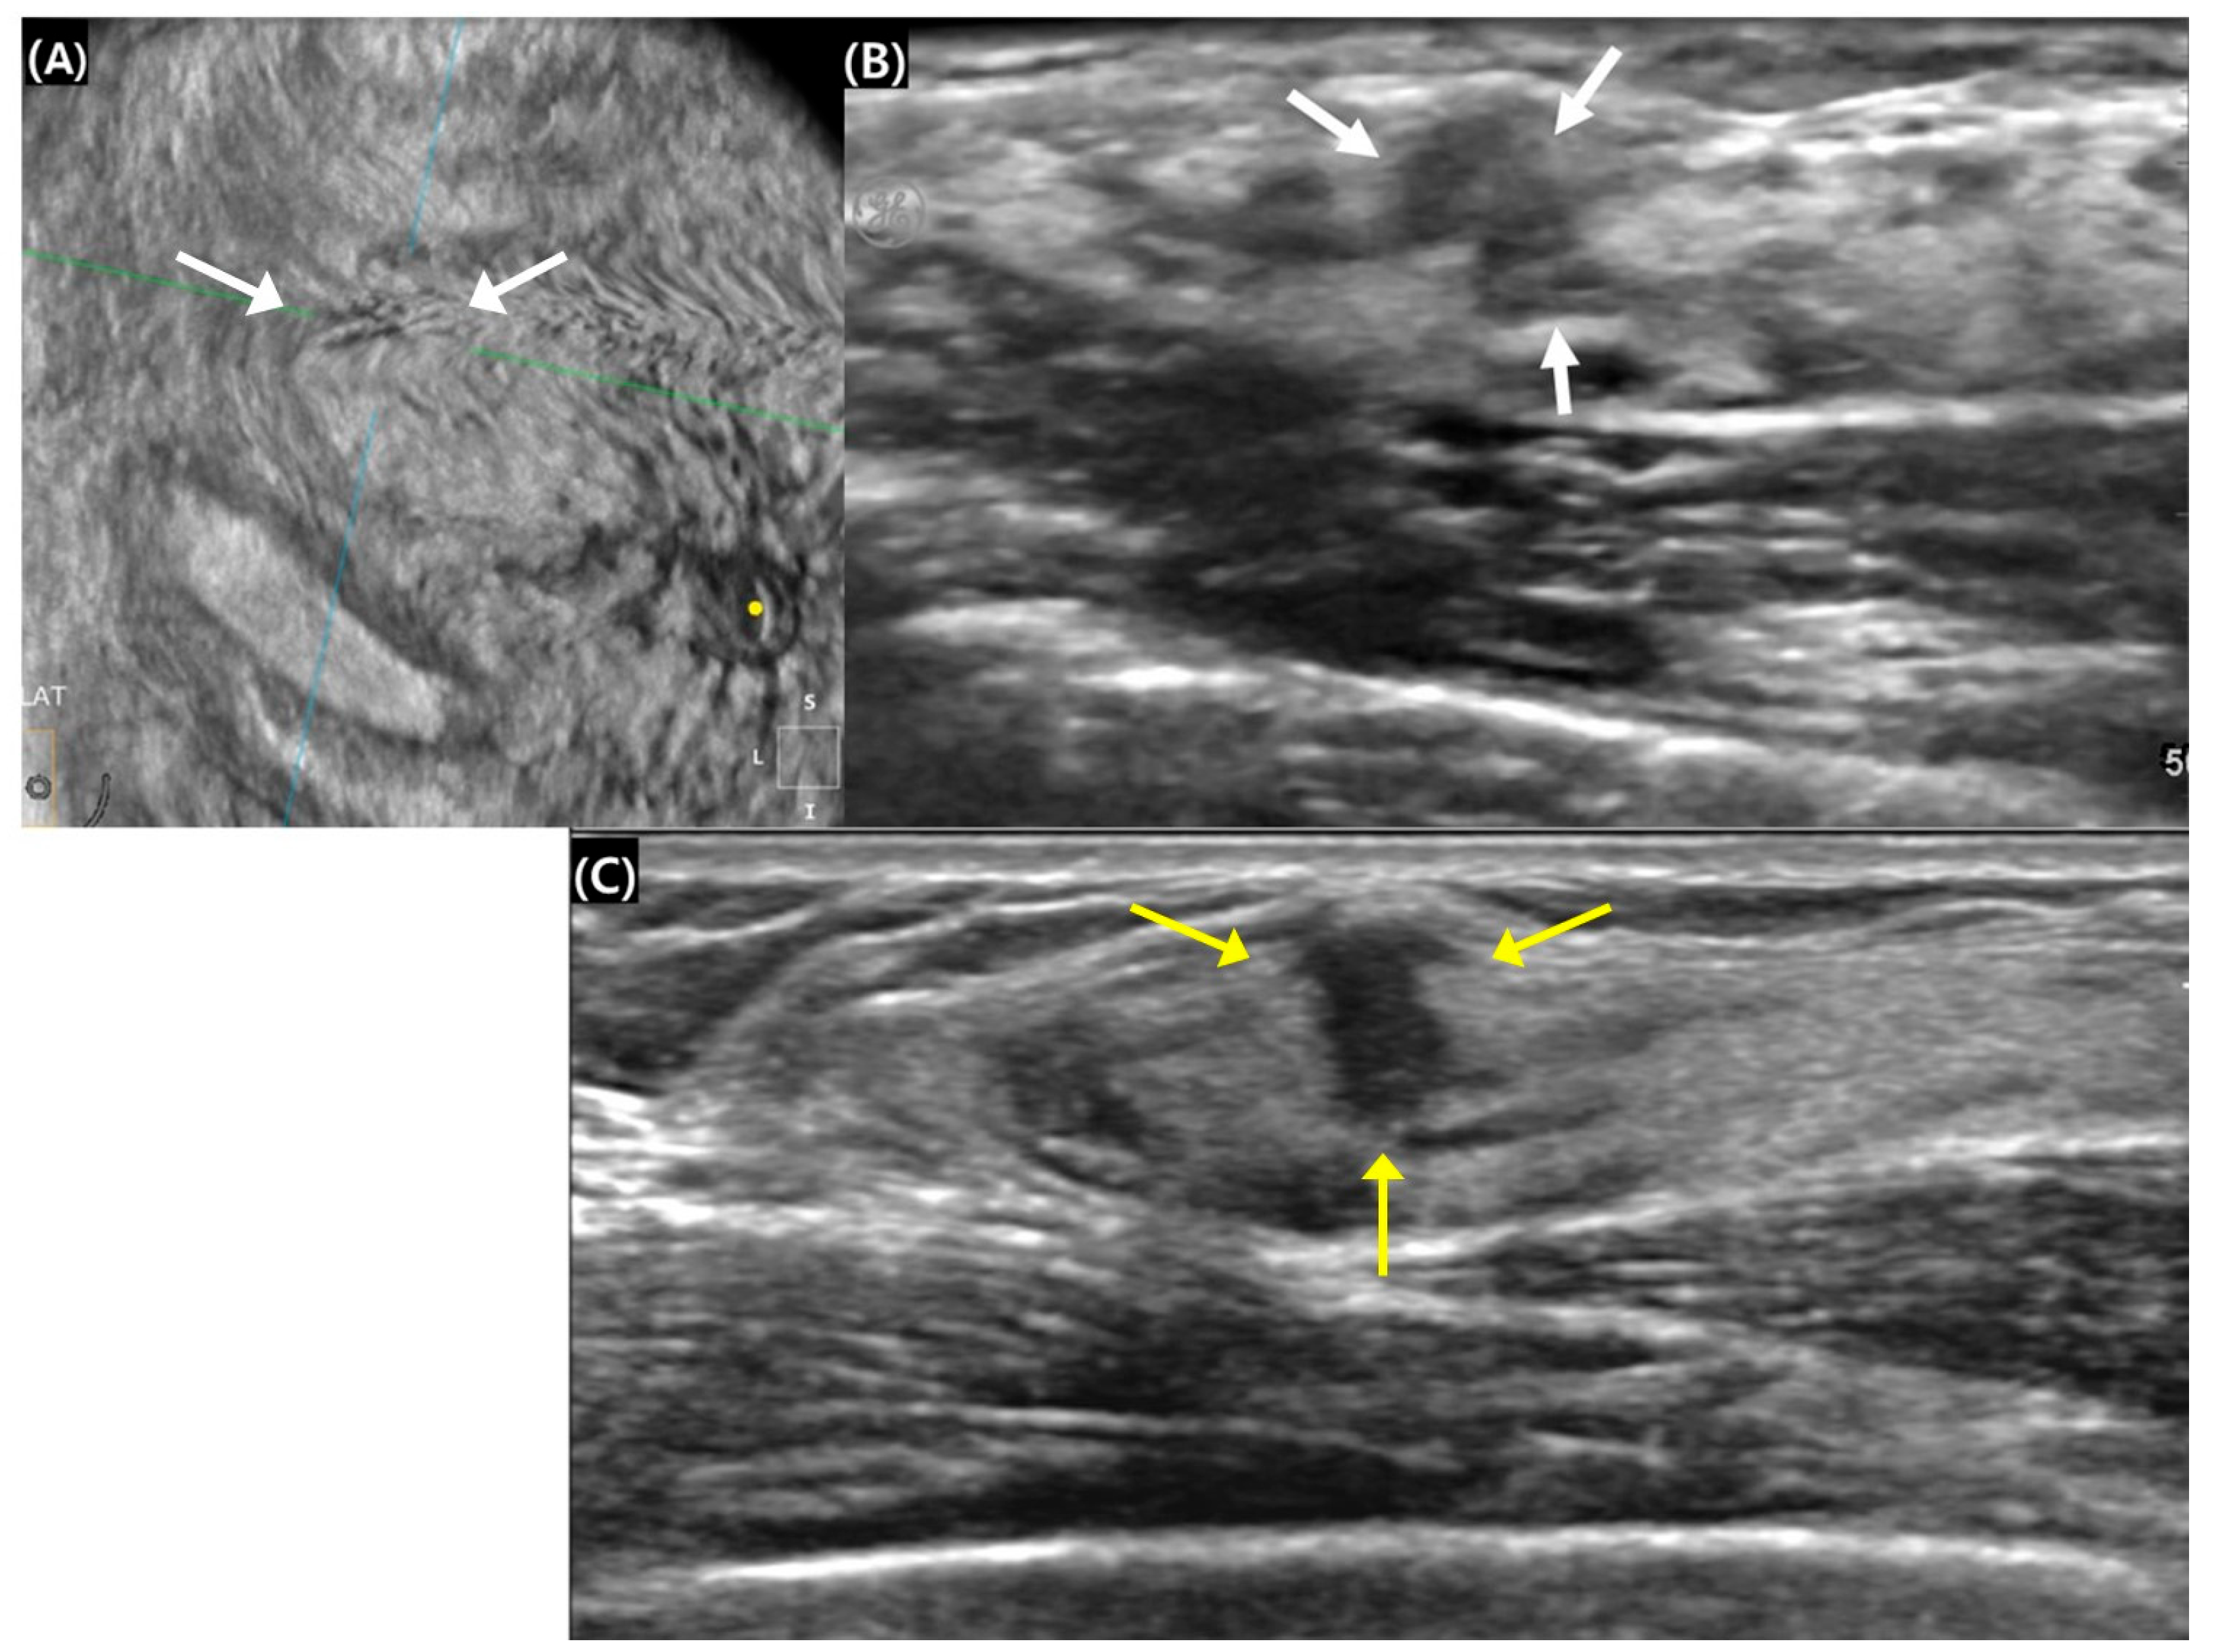

Figure 1.

Surgical histopathology revealed a 0.9 cm invasive ductal carcinoma in the right breast of a 45-year-old woman. (A,B) The 0.8 cm mass with an indistinct margin exhibited isoechogenicity on automated breast ultrasound (white arrows). The green and blue lines served as crossing directional lines to indicate the position and direction of the lesion, and the yellow dot represents the nipple location in (A). (C) The mass appeared to have a 0.9 cm spiculated margin with hypoechogenicity on handheld breast ultrasound (yellow arrows). The lesion’s width was 0.5 cm, and the height–width ratio was calculated to be 1.8.

A comparison of US findings between ABUS and HHUS is summarized in Table 1. All lesions evaluated with ABUS were classified as having an irregular shape, resulting in no variability for the statistical analysis of ABUS–HHUS agreement. In contrast, 96.8% of lesions assessed by HHUS were categorized as irregular, further limiting the variability between the two modalities. Regarding margin characteristics, ABUS demonstrated a tendency to show less aggressive margins compared to HHUS, with 61.3% of lesions showing agreement between the two modalities, while 25.8% exhibited fewer suspicious margins on ABUS (Figure 1). However, this difference was not statistically significant (p = 0.221). Regarding the height–width ratio, ABUS showed a slightly higher median value (0.98, interquartile range [IQR]: 0.72–1.12) compared to HHUS (0.86, IQR: 0.74–1.10), although this difference was also not statistically significant (p = 0.166). Additionally, there were no significant differences between ABUS and HHUS in terms of echo patterns and posterior features (p > 0.05), indicating comparable performance in these aspects.